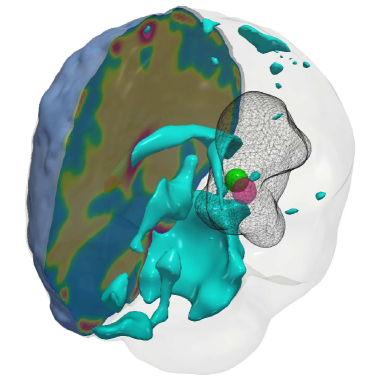

Fig. 6: Qualitative results for the artificial tumor test-case AT-C3 (a multi-focal tumor) with growth parameters ρ=10,κ=0.025formulae-sequencesuperscript𝜌10superscript𝜅0.025\rho^{\star}=10,~{}\kappa^{\star}=0.025. The images show the tumor data (gray wireframe), ground truth tumor initial condition (green volume), reconstructed tumor initial condition (magenta volume), ventricles (cyan volume), and a section of the patient brain geometry. The CS solver activates one of the Gaussians exactly, while assigning smaller activations (not pictured) around the second ground truth Gaussian (similar to the 1D analogous test-case 1D-C2).

Setup. We grow synthetic tumors in the segmentation of a statistical brain atlas [8] MRI scan (an atlas obtain by averaging several MR images). The segmentation labels are gray matter, white matter, and cerebrospinal fluid-filled ventricles (CSF). We use sparse initial conditions to grow the tumor to a significant size resembling clinical observations and invert for all biophysical parameters using the grown tumor at t=1𝑡1t=1 as input data to the solver. For all our test cases, we assume that the tumor grows and diffuses only in white matter. For this test-case, we observe the data everywhere, i.e., cd=0subscript𝑐𝑑0c_{d}=0. We consider the following variations:

(i) AT-C1: medium sized, mono-focal tumor ρ=8superscript𝜌8\rho^{\star}=8 κ=0.025superscript𝜅0.025\kappa^{\star}=0.025

(ii) AT-C2: large sized, mono-focal tumor ρ=12superscript𝜌12\rho^{\star}=12 κ=0.05superscript𝜅0.05\kappa^{\star}=0.05

(iii) AT-C3: multi-focal tumor, nearby seeds ρ=10superscript𝜌10\rho^{\star}=10 κ=0.025superscript𝜅0.025\kappa^{\star}=0.025

(iv) AT-C4: multi-focal tumor, distant seeds ρ=8superscript𝜌8\rho^{\star}=8 κ=0.025superscript𝜅0.025\kappa^{\star}=0.025

We report our quantitative results (performance measures, convergence, and solver timings) in Tab. 4 and visualize the reconstruction to qualitatively assess the performance of our solvers in Fig. 4 - Fig. 7. Each figure shows an isometric view of the patient brain with 3D volumes of the grown tumor data, ground truth, and reconstructed initial condition. We additionally visualize the ventricles and sections of healthy tissue to reveal the heterogeneity of the brain (and hence the tumor).

Observations. We observe that for the medium sized tumor (AT-C1) the reconstruction is nearly perfect for the CS solver while the \mathboldL2\mathboldsubscript𝐿2\mathbold{L_{2}} solver produces a lower performance, particularly in the inversion of the reaction coefficient. This is primarily due to the rich initial conditions produced by the \mathboldL2\mathboldsubscript𝐿2\mathbold{L_{2}} solver which impedes its ability to predict the correct reaction scaling using our method. We note that if the reaction scaling is known beforehand, the \mathboldL2\mathboldsubscript𝐿2\mathbold{L_{2}} solver can potentially have better performance (see [56, 16] for similar synthetic experiments). This problem is magnified for larger tumors (AT-C2 and AT-C3) where the predicted reaction coefficient shows about 66%percent6666\% and 54%percent5454\% relative error in the \mathboldL2\mathboldsubscript𝐿2\mathbold{L_{2}} solver for the two test-cases respectively (as compared to around 15%percent1515\% and 1%percent11\% error with sparsity constraints). The reconstruction in diffusivity also suffers similarly without enforcing sparsity. The final test-case shows a multi-focal tumor with two far apart proliferation sites. While both the solvers produce disjoint initial conditions for the tumor, the CS solver does better in reconstructing the model parameters: 2% versus 37% relative error in diffusivity and 9% versus 50% relative error in reaction coefficient. Both solvers show similar performance in their ability to fit the data (as measured by the relative error in final tumor reconstruction). Hence, our synthetic observations show consistent improvement in target parameter estimation for all test-cases with sparse initial conditions, without sacrificing the final tumor reconstruction quality.